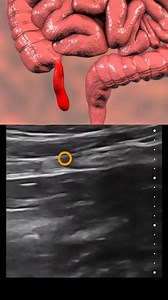

Appendix Ultrasound Reporting | Appendicitis Scan Reports | How To Write USG Report | Abdominal USG *Cases: Intro - 0:00 Acute Appendicitis - 0:07 Appendicitis with

Dr. Sam's Imaging Library. . Appendix Ultrasound Reporting | Appendicitis Scan Reports | How To Write USG Report | Abdominal USG *Cases: Intro - 0:00 Acute Appendicitis - 0:07 Appendicitis with Appendicolith - 1:55 Perforated Appendix - 4:33

9.9K views · 43 reactions | Appendicitis | Ultrasound signs. | Med G | Facebook

4.6K views · 22 reactions | Appendicitis | Ultrasound signs. Part 2 | Med G | Facebook

3.8K views · 13 reactions | Appendicitis | Ultrasound signs. Part 1 | Med G | Facebook